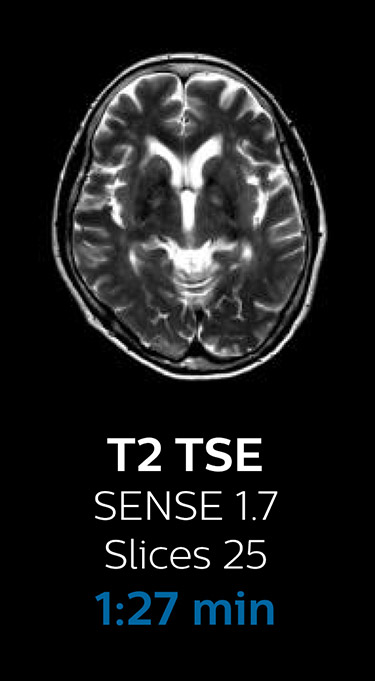

Scanning time reduction in brain MRI with Compressed SENSE

Fast MRI of brain

With Compressed SENSE, the scan time for the routine brain examination at KNC was reduced from 15:48 to 10:19 minutes, which corresponds to 35% reduction.

Ingenia 3.0T CX

Scan time 15:48 min.

Brain with Compressed SENSE

Ingenia 3.0T CX

Scan time 10:19 min.